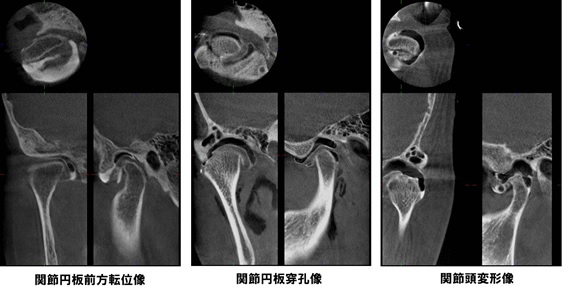

顎関節症は放置すると、初期の関節炎から、関節円盤の癒着・穿孔・転位、変形性関節症と病態が進んでいくことがわかってきました。

顎関節造影検査

検査所見